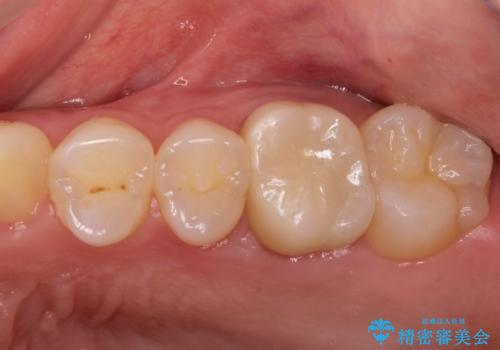

金属の奥歯 → 白い奥歯 根管治療からのやり直し

- 再根管治療→土台の築造 を行った上でのかぶせ物のやり替えをおこないました。

神経の無い歯のかぶせ物をやり替える際は、是非根管治療からしっかりやり直すことをおすすめします。

かぶせ物の種類:Bellezza